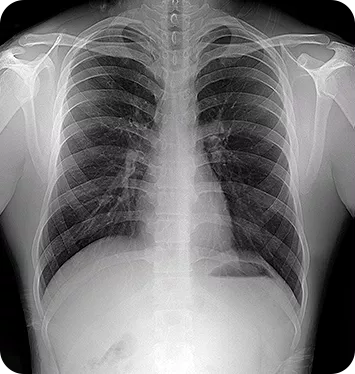

Πρόκειται για ένα πλήρες σύστημα, έτοιμο για άμεση δράση σε οποιοδήποτε περιβάλλον. Περιλαμβάνει την ψηφιακή γεννήτρια, προηγμένο ανιχνευτή LG και ενσωματωμένη Τεχνητή Νοημοσύνη (AI) για αυτόματη βελτιστοποίηση εικόνας. Η Nooka προσφέρει κρυστάλλινη ανάλυση με ελάχιστη δόση ακτινοβολίας, καθιστώντας την ιδανική για κινητές μονάδες, ναυτικές αποστολές και εμπόλεμες ζώνες.

Το σύστημα MINE ALNU (Nooka) αποτελεί το απόλυτο αποκορύφωμα στον τομέα της φορητής ψηφιακής ακτινογραφίας παγκοσμίως. Σχεδιάσαμε το Nooka για να καλύπτει τα πιο αυστηρά διεθνή πρότυπα ιατρικής απεικόνισης. Επιπλέον, προσφέρει απαράμιλλη ευελιξία χωρίς κανέναν συμβιβασμό στην ποιότητα. Η διαγνωστική ακρίβεια που παρέχει είναι εξαιρετική και απόλυτα αξιόπιστη.

Ως εκ τούτου, είναι η ιδανική λύση για διαγνωστικούς ελέγχους εν κινήσει και σε δύσβατα σημεία. Παράλληλα, το σύστημα συνδυάζει την προηγμένη τεχνολογία των ψηφιακών ανιχνευτών της LG. Αυτοί οι ανιχνευτές διατίθενται σε ενσύρματη αλλά και σε ασύρματη μορφή. Επομένως, εξασφαλίζουν την παραγωγή κρυστάλλινων εικόνων υψηλής ανάλυσης σε κάθε εξέταση.

- Απεικόνιση υψηλής ανάλυσης: Παράγει εξαιρετική ποιότητα εικόνας με ανώτερη ανάλυση λεπτομέρειας